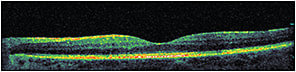

At the first visit, ordering OCT (particularly when best-corrected visual acuity is less than 20/20) is important because it will help us to document and learn about the pattern, location, thickness (Figures 1 and 2), and vitreomacular interface status of the edema, all of which can affect our treatment plan and visual prognosis.

Figure 1. Pretreatment OCT of diabetic macular edema.